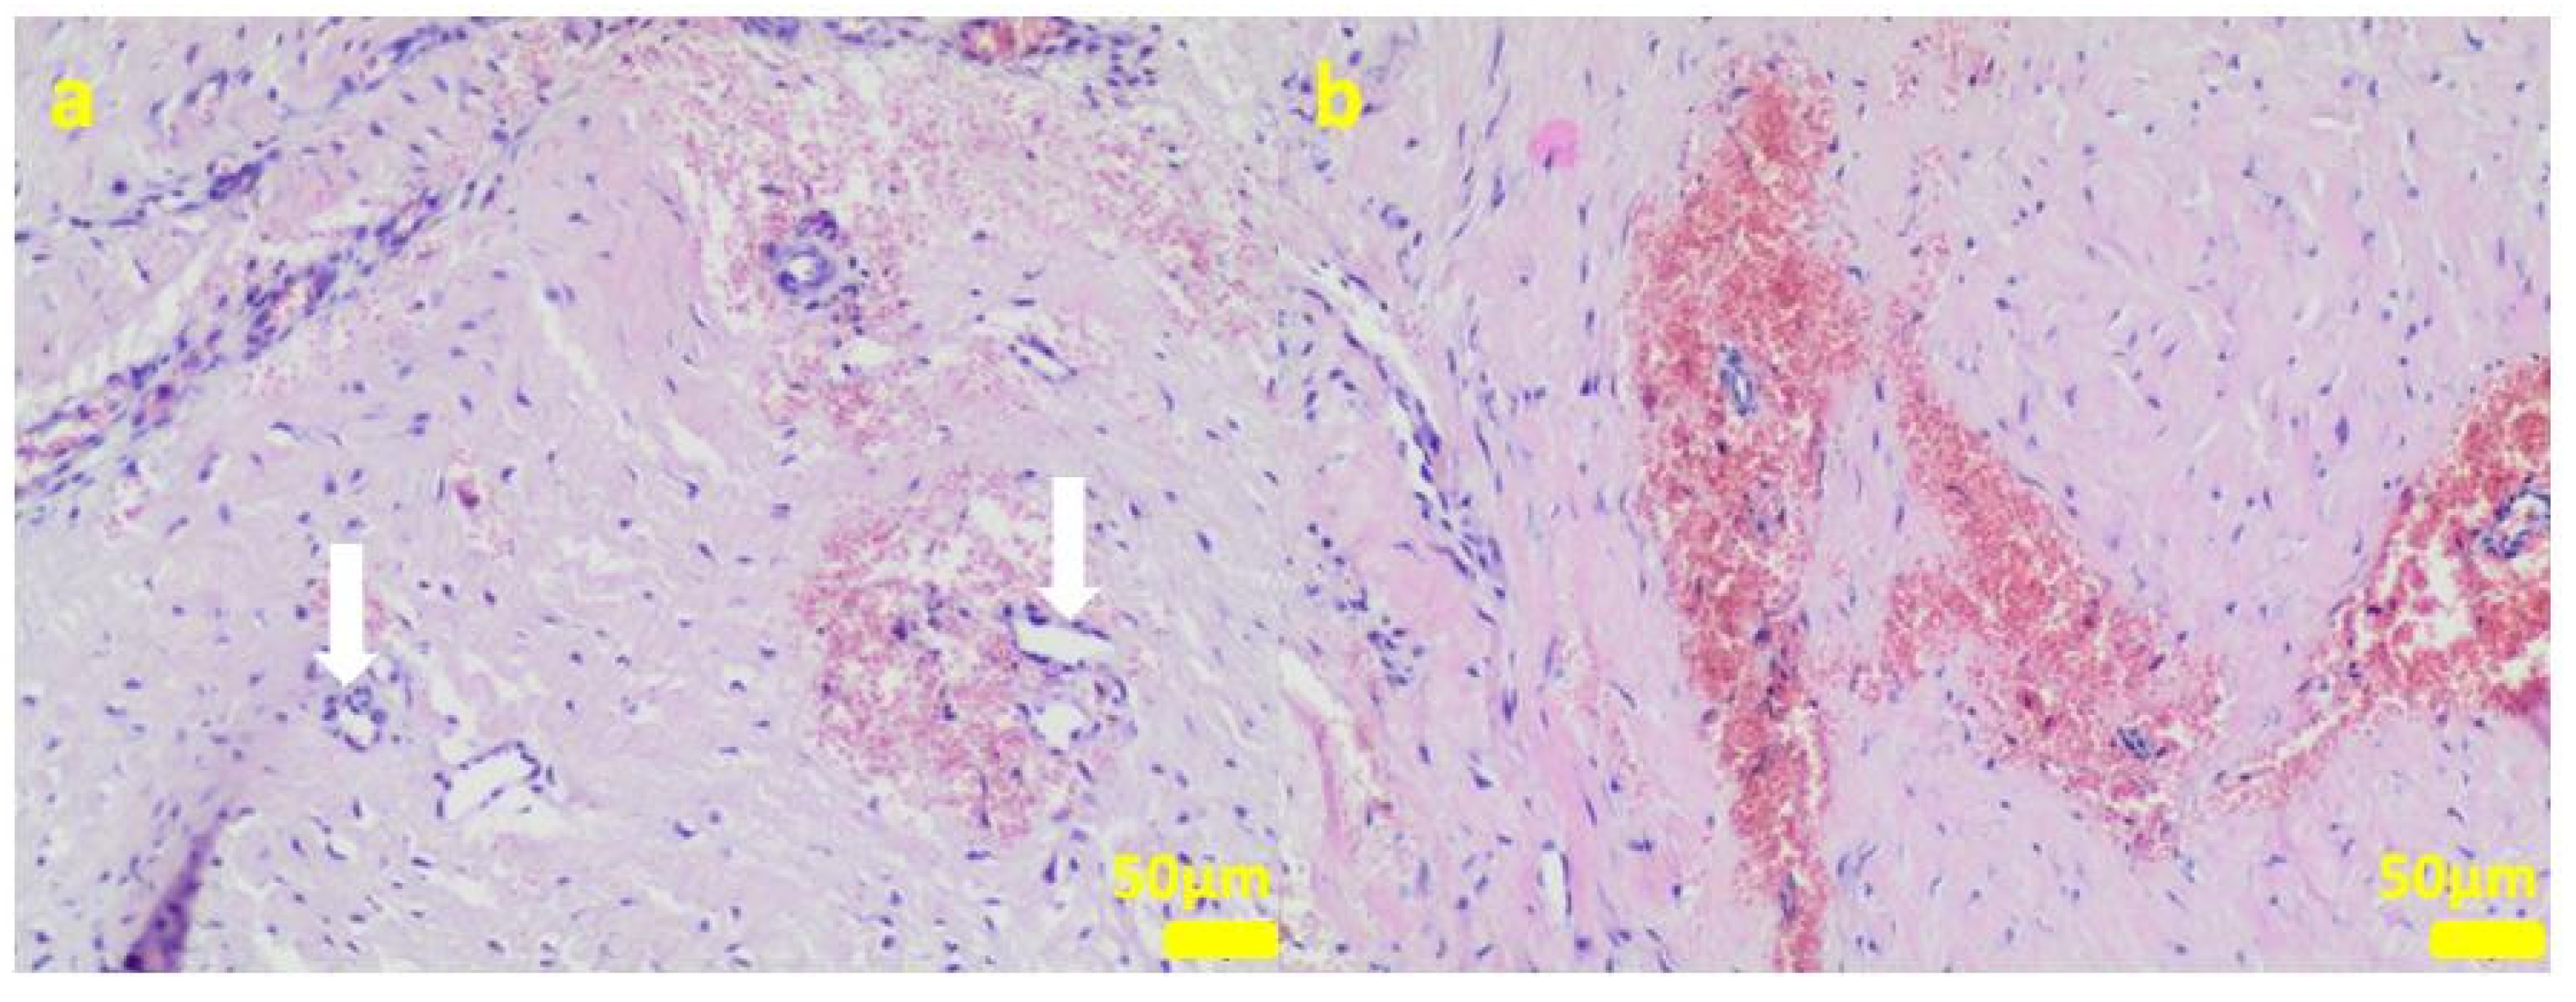

Sample 3:the compact fibrous connective tissue (a). Sample 4:the compact fibrous connective tissue with fine fibrillar material and black pigment (white arrow; (b)). Hematoxylin-eosin staining, magnification 100×.

Figure 9.

Sample 5:at the sample periphery, the fibrous connective tissue abundant in small blood vessels (white arrows) with areas of maturation to compact fibrous tissue (a), and multifocally hemorrhages (b). Hematoxylin-eosin staining, magnification 100×.

Figure 10.

The microscopic lesions observed in the examined samples suggested the correct tissue reparation process, starting from the granulation tissue up to the mature compact fibrous tissue that is typical for postsurgical scars. The implant, i.e., the TPLO plate and screws covered in the hybrid layer containing silver nanoparticles, seemed to facilitate the healing process; therefore, some features of granulomatous inflammation and plasmocytic perivascular infiltrates were present in the examined samples. Generally, both such microscopic findings and soft tissue calcification processes are observed in a natural healing process.